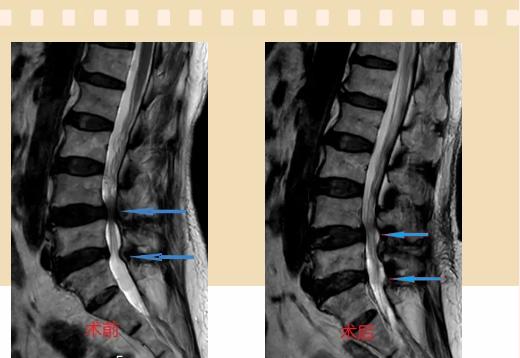

入院后李鵬副主任醫(yī)師為其進行了詳細的查體,完善了術前的檢查,明確診斷為:腰椎管狹窄癥(L4/5、L5/S1),病人合并2型糖尿病,請內分泌科會診,穩(wěn)定血糖后,麻醉科會診病人,排除手術禁忌,李鵬為病人制定了手術方案:單側入路雙側減壓(ULBD)。

手術采用三個微創(chuàng)小切口,兩個節(jié)段減壓手術時間2.5小時,出血50ml。術后2天腰圍保護下床活動,術后5天順利出院。

傳統(tǒng)腰椎管狹窄癥的手術治療,往往需要切開減壓,同時需要內固定融合術,創(chuàng)傷很大,同時可能需要輸血,臥床時間較長,病人合并糖尿病,感染風險也高,而本次采用的UBE-ULBD手術切口更?。悠饋砑s3cm,如果是單節(jié)段狹窄只需要不到2cm切口)、創(chuàng)傷更小,術后恢復較快,可以更早地恢復正?;顒?。

此外,手術保留了病變節(jié)段的穩(wěn)定性,是一種微創(chuàng)的椎管減壓手術,能通過切除部分椎板、關節(jié)突關節(jié)、黃韌帶來解除神經根和硬膜囊的壓迫,不需要額外行腰椎內固定術,不需要螺釘及融合器的植入,病人術后腰椎的活動度不受影響。(盧   闖  劉   旭   袁錦鈺)